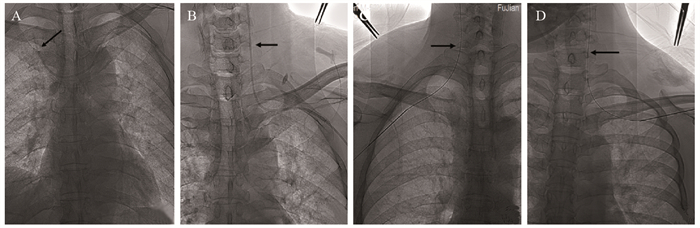

方法 回顾性分析在福建省肿瘤医院就诊并接受超声联合DSA引导下行单切口经AV入路TIVAP植入术的240例患者临床资料。记录手术相关信息,包括AV宽度、AV穿刺成功率、植入成功率、超声引导穿刺时间、手术时间及术中、术后并发症等。

结果 240例患者均成功植入TIVAP,植入成功率100%。229例患者于超声联合DSA引导下行单切口经AV穿刺植入TIVAP,AV穿刺成功率95.42%(229/240),11例因AV穿刺失败,改超声联合DSA引导下经同侧颈内静脉(IJV)穿刺植入TIVAP。240例患者术前超声探查定位下测得拟穿刺段AV平均宽度为(7.56±1.26)mm,其中AV 1次穿刺成功195例,2次穿刺成功26例,3次穿刺成功8例,成功率分别为81.25%、10.83%、3.34%;超声引导下平均穿刺时间(0.85±0.52)min,手术平均时间(25.9±4.8)min。术中并发症发生率为1.67%(4/240),未发生血胸、血气胸及严重致死性并发症;TIVAP留置期间相关并发症发生率为2.92%(7/240),未见导管相关血流感染、导管相关静脉血栓、导管断裂/移位、夹闭综合征、药物外渗等并发症发生。

Results All 240 patients were successfully implanted with TIVAP, and the success rate was 100%. In 229 cases, TIVAP was implanted through single-incision AV puncture under the guidance of ultrasound combined with DSA, and the success rate of AV puncture was 95.42% (229/240). In 11 cases, TIVAP was implanted through the ipsilateral internal jugular vein (IJV) under the guidance of ultrasound combined with DSA due to the failure of AV puncture. In the 240 patients, the average width of AV of the intended puncture segment was (7.56±1.26) mm measured by preoperative ultrasound exploration and positioning, in which 195 cases were successfully punctured once, 26 cases were successfully punctured twice, and 8 cases were successfully punctured three times, with the success rate of 81.25%, 10.83% and 3.34%, respectively. The average puncture time under ultrasound guidance was (0.85±0.52) min, and the average operation time was (25.9±4.8) min. The incidence of intraoperative complications was 1.67% (4/240). No hemothorax, hemopneumothorax or serious fatal complications occurred. The incidence of complications during TIVAP retention was 2.92% (7/240). No complication such as catheter-related bloodstream infection, catheter-related venous thrombosis, catheter rupture/displacement, clipping syndrome or drug extravasation was observed.